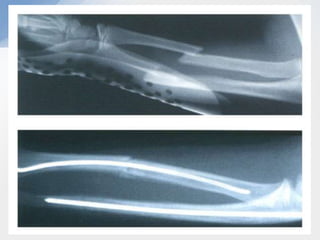

Monteggia

• Fracture of the proximal ulna with dislocation of the

radial head

• Bado classification

1.   Anterior dislocation/ anterior angulation (60%)

2.   Posterior dislocation/ posterior angulation (15%)

3.   Lateral dislocation/ lateral angulation (20%)

4.   Anterior dislocation/ both bone proximal # (5%)

Monteggia • Fracture ofthe proximal ulna with dislocation of the radial head • Bado classification 1. Anterior dislocation/ anterior angulation (60%) 2. Posterior dislocation/ posterior angulation (15%) 3. Lateral dislocation/ lateral angulation (20%) 4. Anterior dislocation/ both bone proximal # (5%)